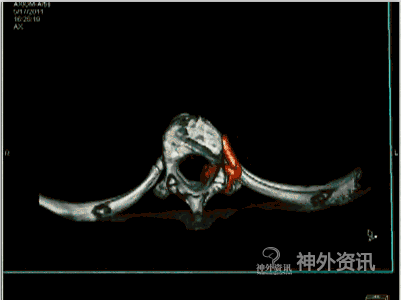

图4: I. 动态双容积重建轴位融合影像。

图4: J~L. 最大密度投影(MIP)冠状位、矢状位和轴位融合影像。

图4: M. 动态旋转MIP。

图4: N~P. MRI/3D-DSA 三维融合冠状位、矢状位和轴位融合影像。